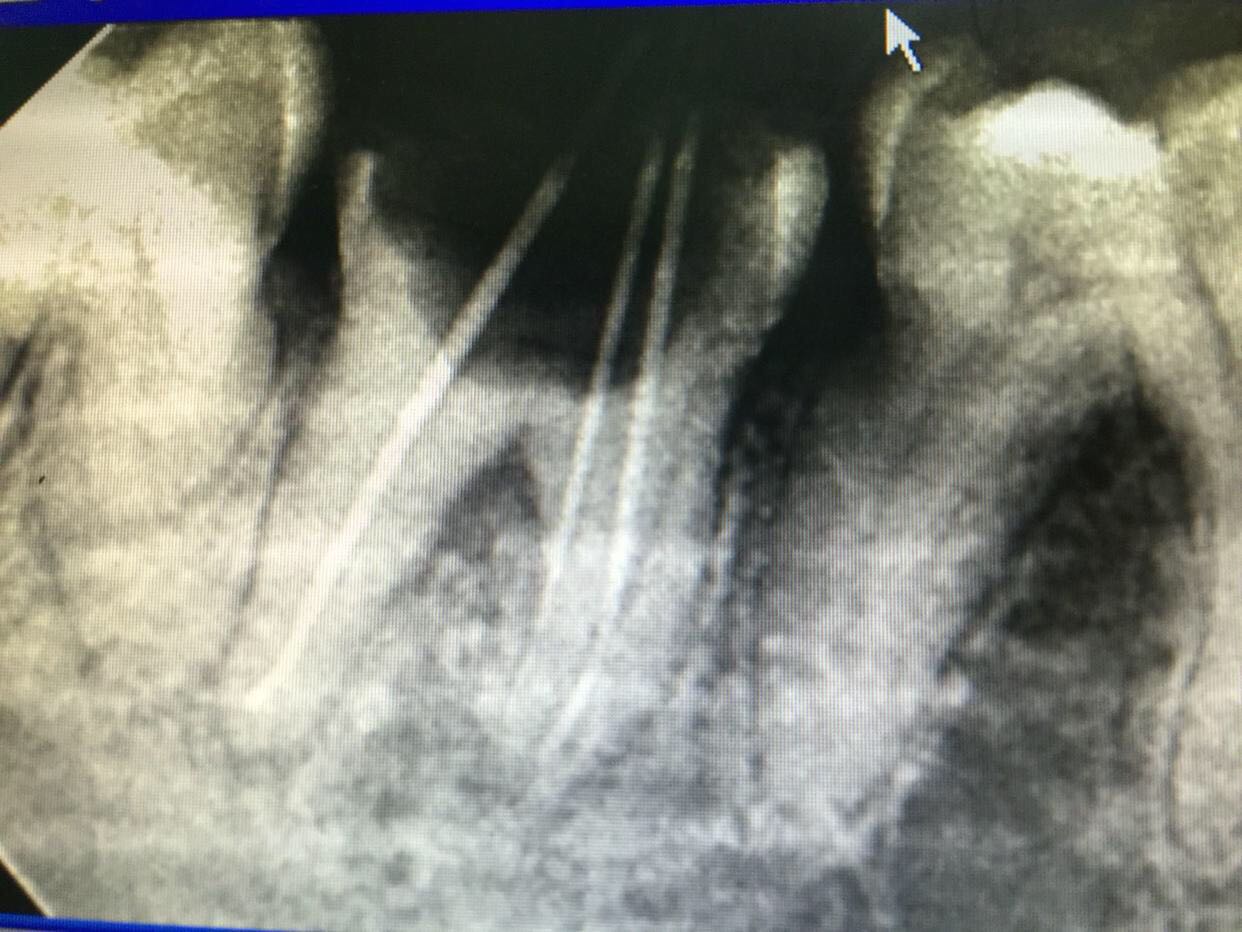

检查:47颊合面深龋,探及穿髓,探痛无,牙龈未见明显红肿,冷诊(-)。X线片示:47根尖区低密度影像。

诊断:47慢性根尖周炎 治疗:47去龋净,开髓揭顶全,拔髓,疏通根管,测长,根管预备,冲洗,干燥,试尖,根管封药,告医嘱,肿痛随意。